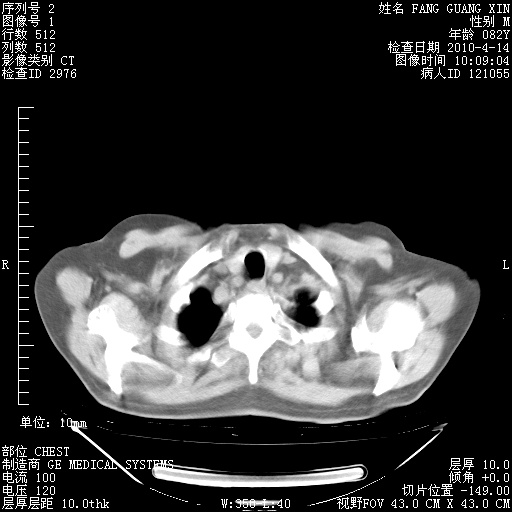

4月14日肺部CT